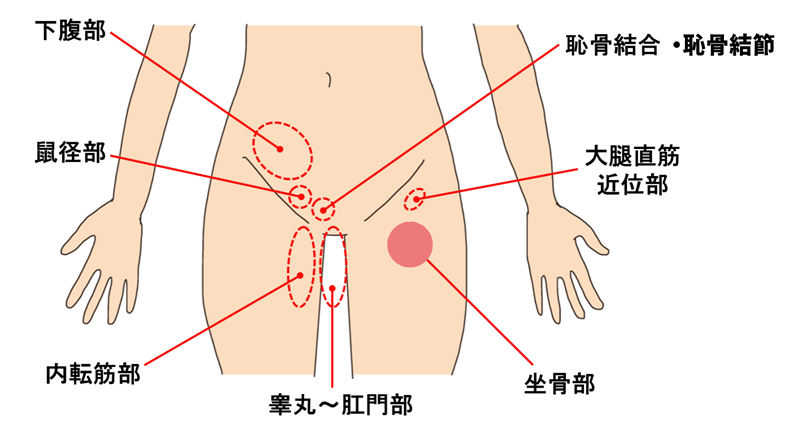

「股関節が痛い」と言っても、実は痛む場所は人によってかなり違うと言われています。

まずは、「どこが一番気になるか」を整理してみましょう。

たとえば、

「足の付け根(鼠径部)がズーンと痛む」

「股関節の外側が張るように痛い」

「お尻の奥が重だるい感じがする」

こうした違いだけでも、考えられる負担のかかり方が変わってくるそうです。

会話でも、

「股関節だと思ってたけど、実は太ももの付け根だった」

「お尻の奥が原因だと知って少し納得した」

という声はよく聞かれます。

痛みの場所を言葉にできるかどうかが、原因を考える第一歩になると言われています。